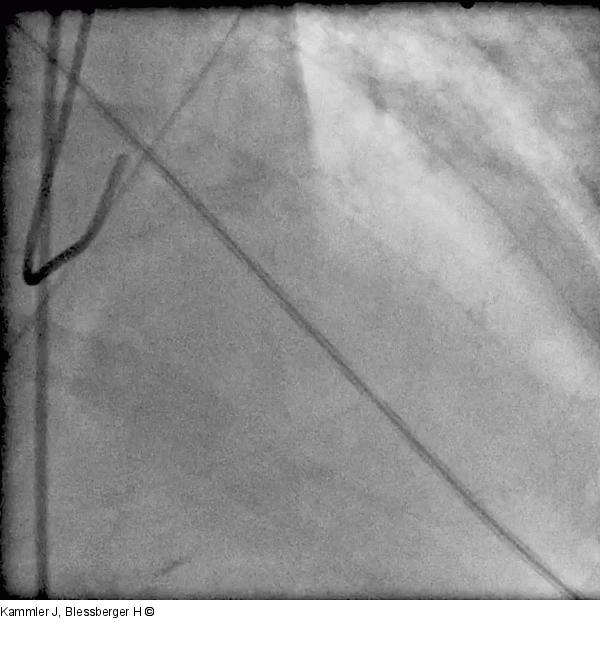

Kammler J, Blessberger H

Ischämischer Ventrikelseptumdefekt bei Vorderwandinfarkt - Fallbericht über eine Komplikation mit hoher Mortalität

Journal für Kardiologie - Austrian Journal of Cardiology 2015; 22 (1-2)

: 28-31

Abbildung 11: Film 7